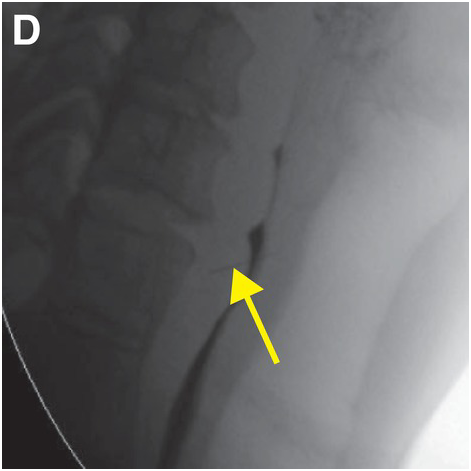

Mri and Ct Atlas of Correlative Imaging in Otolaryngology,

Mri and Ct Atlas of Correlative Imaging in Otolaryngology, Atlas of Small Animal CT and MRI: 9781118446171: Medicine,

Atlas of Small Animal CT and MRI: 9781118446171: Medicine, Diagnostic Imaging of the Head and Neck: MRI with CT & PET,

Diagnostic Imaging of the Head and Neck: MRI with CT & PET, Establishing a Clinical Protocol for Velopharyngeal MRI and,

Establishing a Clinical Protocol for Velopharyngeal MRI and, Otolaryngology (Section 3) - Emergency Radiology COFFEE Case

Otolaryngology (Section 3) - Emergency Radiology COFFEE Case

MRI and CT Atlas of Correlative Imaging in Otolaryngology Flanders, Adam E、 Rao, Vijay M; Tom, Barry M

CRC Press

Flanders Adam E

1992/01/01

1853170372

9781853170379